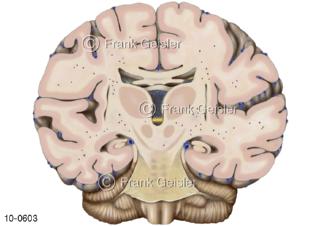

Bildergalerie Nervensystem

Bilder zum Nervensystem,dem Gehirn, Teil des zentralen Nervensystem, Zentralnervensystem ZNSmit Rückenmark, Abbildungen zum Nervengeflecht (Nervenplexus), die Verflechtungen von Nervenfasern, aus der Wirbelsäule hervortretende Nervenäst sowie Nervenzellen der Nerven